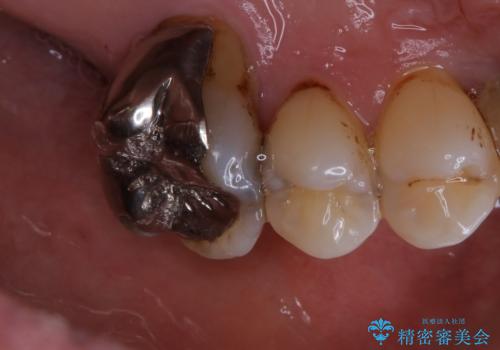

施術後の歯の表面に、茶色く色が残っている所がありますが、これは詰め物の変色の所と、虫歯になっている所です。以前に、CR(コンポジットレジン)による虫歯治療がされています。

CRは経年的劣化や、着色してしまうことがあります。PMTCでクリーニングを行うと、古いCRが目立つことがあるため、気になる際は詰め替えを行います。

茶色くなっている部分が、着色なのか、劣化なのか、虫歯によるものなのかは判別が難しいことがあります。そのため、定期的にPMTCを行うことで状態の確認が的確に行えます。

また、治療が開始される前などにも、全体的にクリーニングを行いご自身本来の歯の色、状態を精密に確認することが大切です。